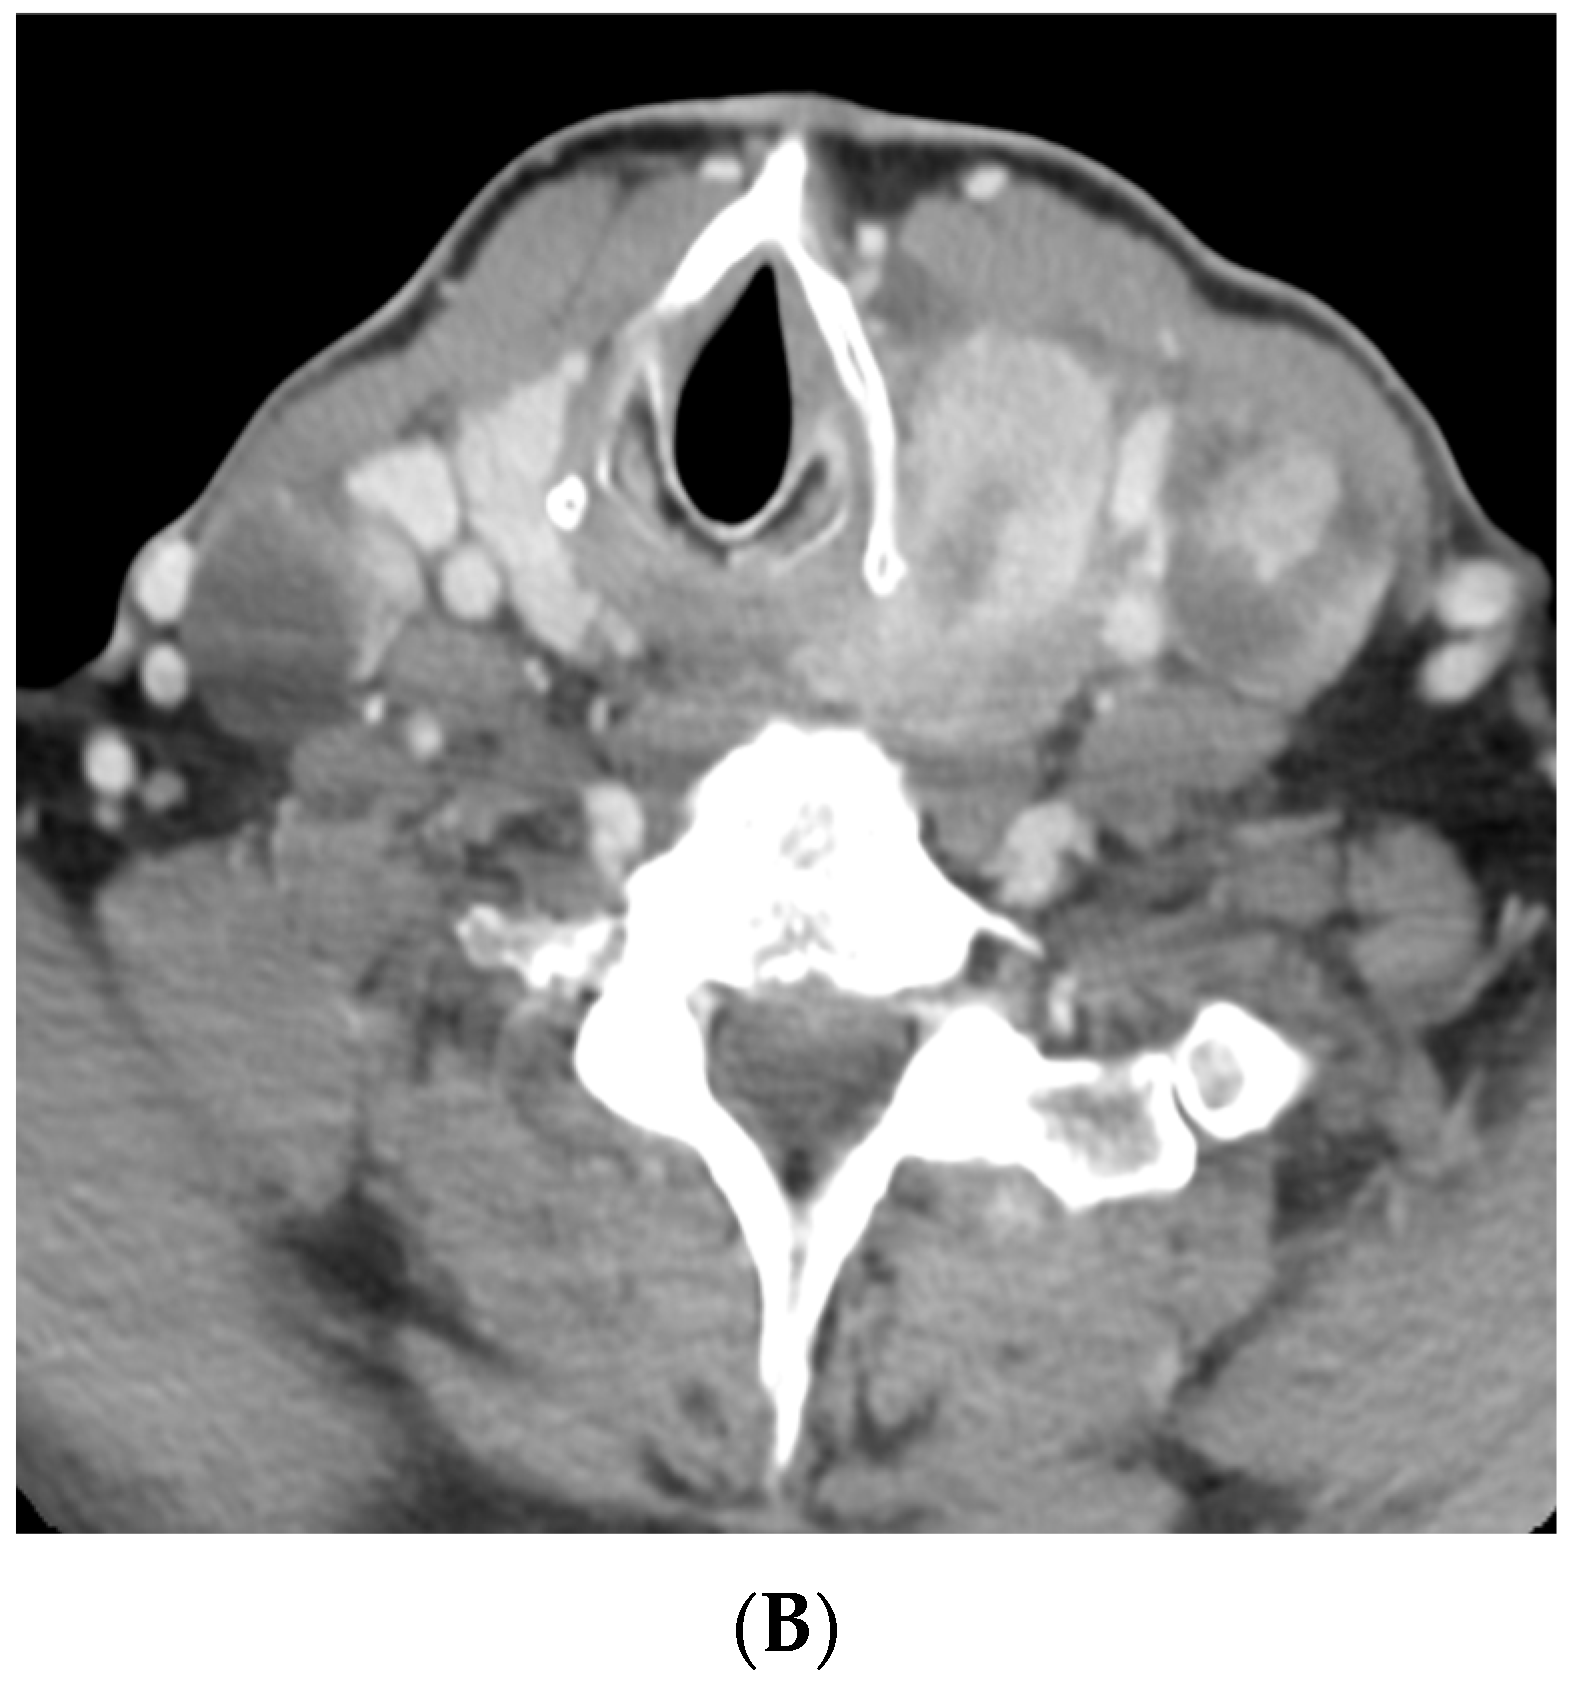

As outlined by the accompanying patient testimony, a 65-year-old gentleman presented with a 6-week history of dysphagia. Computed tomography (CT) imaging of the thorax, abdomen, and pelvis, and magnetic resonance imaging (MRI) of the neck revealed a 7.2 centimeter (cm) mass centered in the left lobe of the thyroid. The mass involved the cervical esophagus and posterior tracheal wall, leading to moderate cervical tracheal airway narrowing and invasion of both the prevertebral fascia and the posterior arch of the cricoid with metastatic right level 2, bilateral level 3, and bilateral level 4 neck nodes (shown in Figure 1 and Figure 2). A 12 millimeter (mm) right hilar node and right paratracheal and subcarinal nodes of less than 10 mm were suspicious for malignant involvement (Stage IVC) [13].

Figure 1.

Pre-treatment CT imaging demonstrated a heterogeneous mass centered in the left thyroid with enhancing, calcified, and hypo-enhancing components invading the esophagus and trachea with enhancing neck adenopathy (A,B). (A) Axial image at the level of the second thoracic vertebra. (B) Axial image at the level of the sixth cervical vertebra.